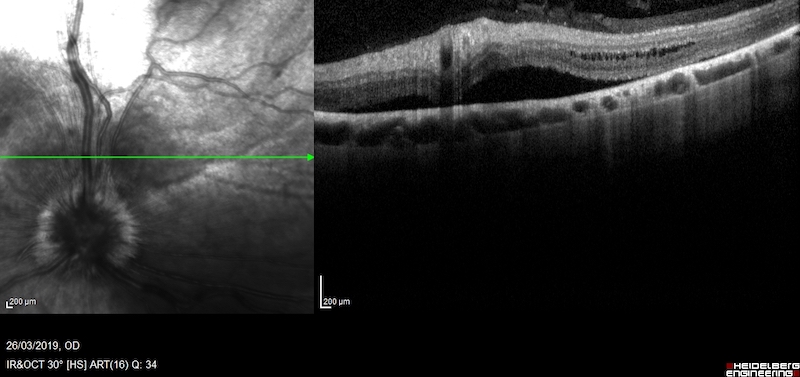

Pero hay determinados tipos de inflamaciones, especialmente de la coroides, que no se pueden ver bien con los signos clínicos externos. En estos casos hay que realizar pruebas especiales como la ecografía ocular, OCTs del segmento posterior o angiografía fluoresceínica.